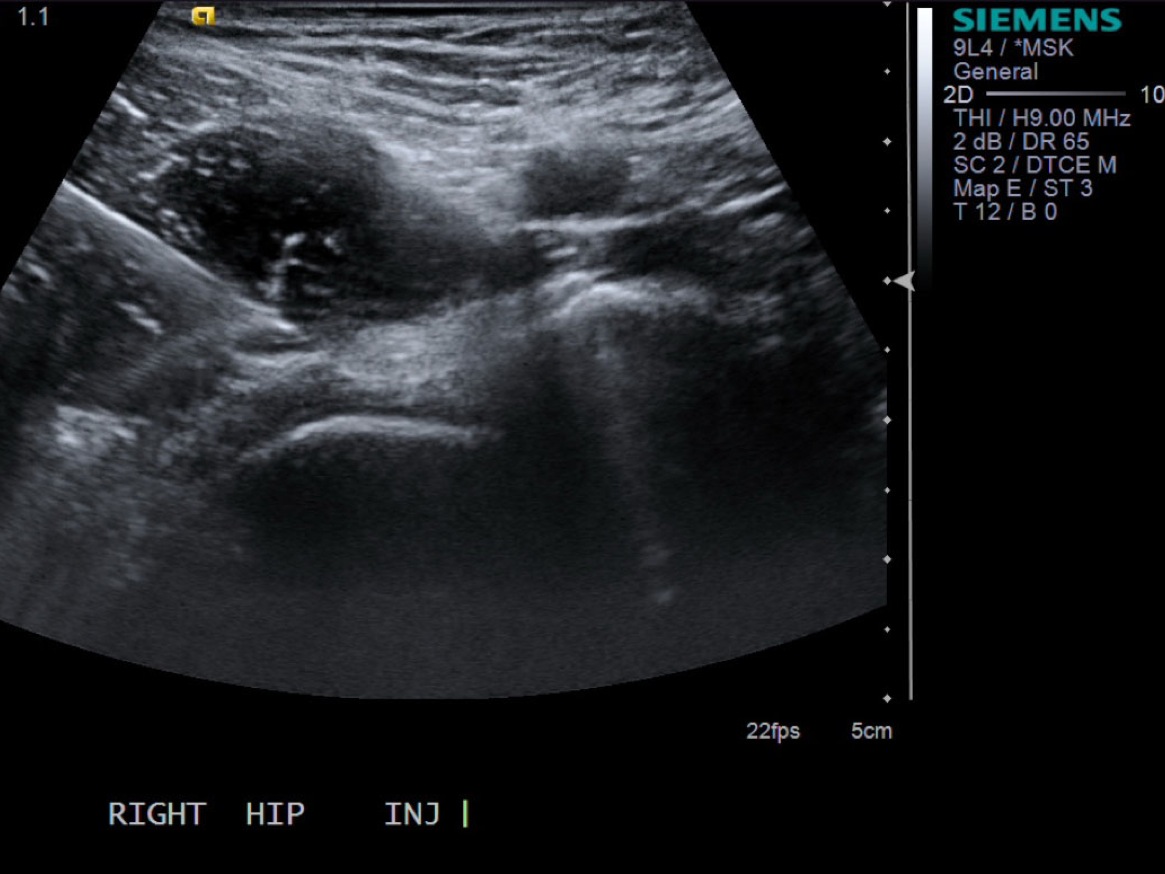

• Probe: 6Mhz Curved

2.Position patient supine.

3.Scan transverse. The iliopsoas tendon inserts on the lesser trochanter. If there’s an iliopsoas bursa filled with fluid, can aspirate/inject that fluid or do a peritendinous injection for tendinosis. Approach laterally.

Transverse/short axis view of iliopsoas tendon

• descriptiondescription